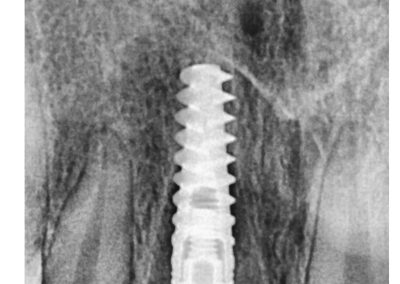

Photo Gallery